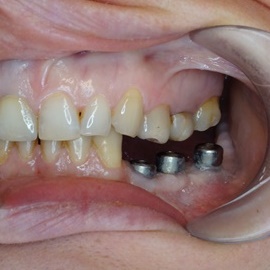

Pacjentka głosiła sie do naszego gabinetu do leczenia z osadzonym mikroimplantem w pozycji lewej dolnej dwójki. Siostrzany implant w pozycji prawej dolnej dwójki wypadł wcześniej, około 1,5 roku od implantacji. Odtworzono przedsionek i dziąsło rogowaciejące, osadzono dwa implanty, jednoczasowo z regeneracją kości. Dopiero na etapie ostatecznej rekonstrukcji protetycznej usunięto zachowany mikroimplant. To się nazywa motywacja do leczenia! Pacjentka przygotowywała sie na ślub prawnuczki :)